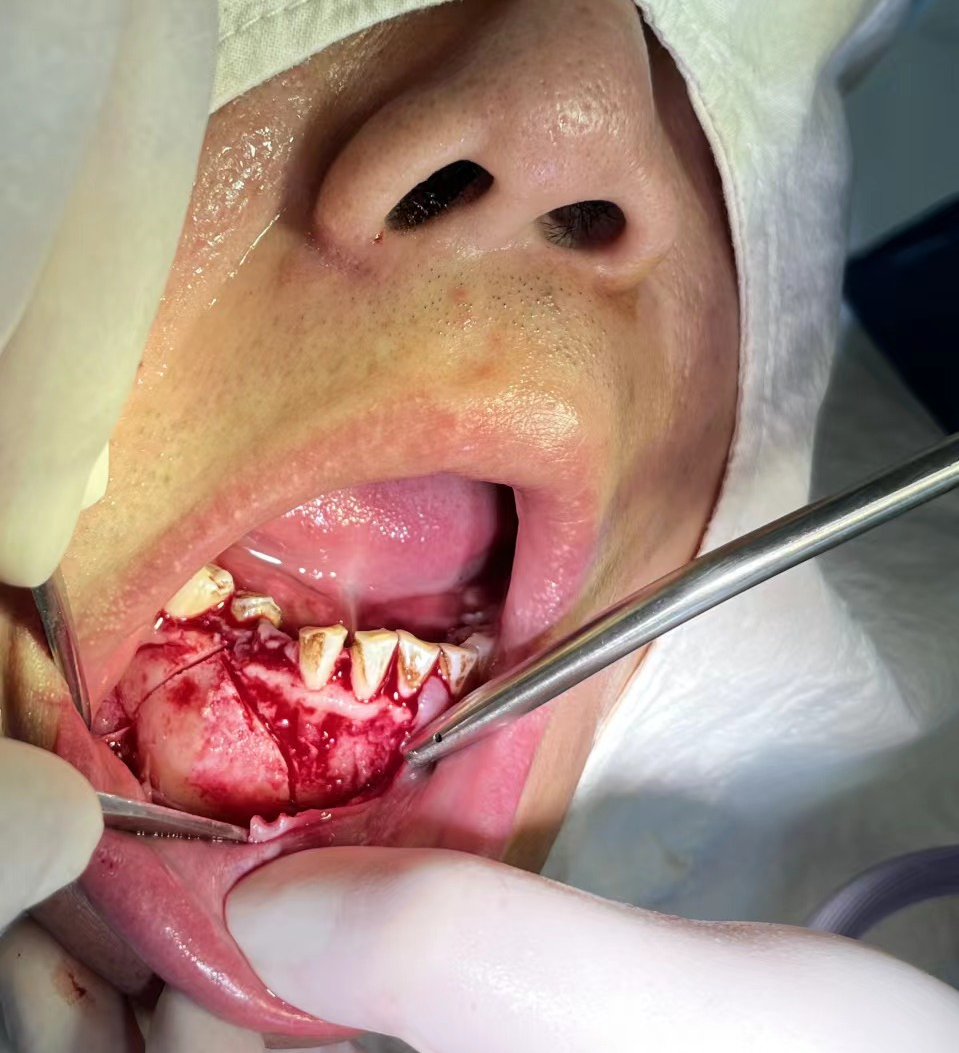

▲術後(hòu)一周患者返院拆線,傷口愈合良好(hǎo)